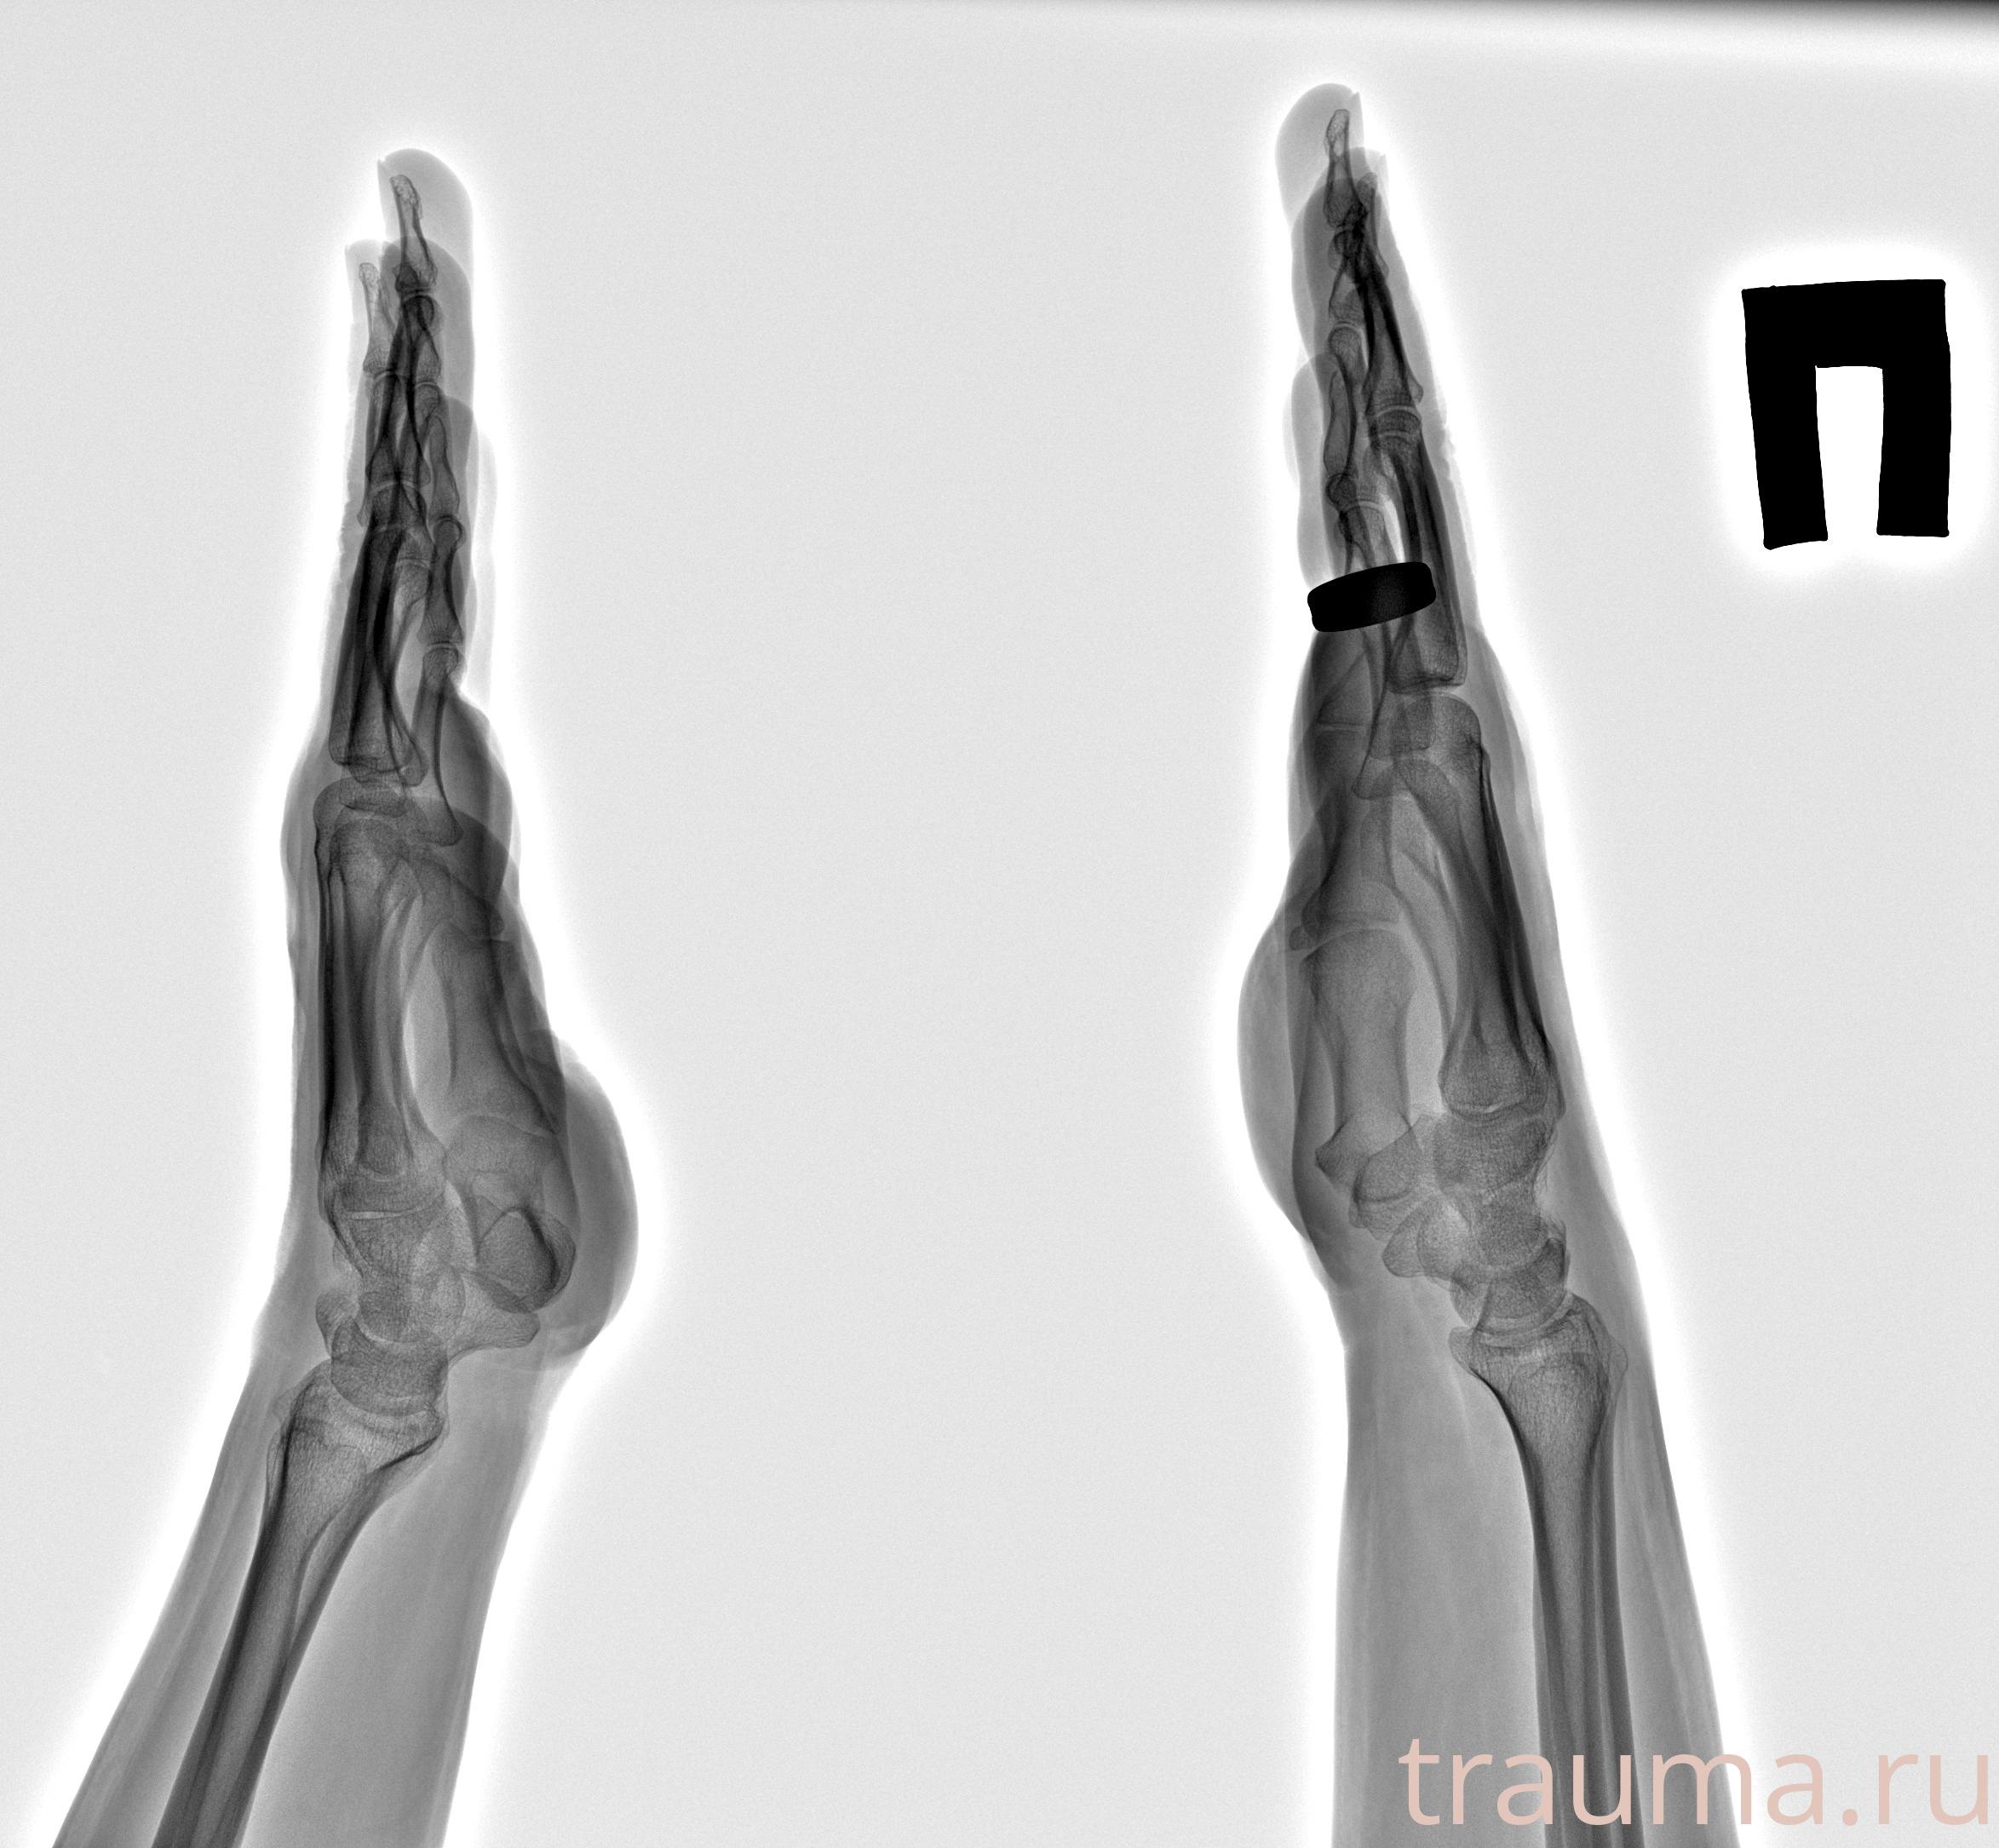

Рентген на дому: по вашему адресу приезжает врач-рентгенолог, травматолог-ортопед с мобильным рентгеновским аппаратом, проводит диагностику травмы или заболевания, делает необходимые рентгенограммы, дает рекомендации по дальнейшему лечению. Получить качественные снимки в домашних условиях возможно благодаря уникальной методике, разработанной МосРентген Центром для института  Склифосовского